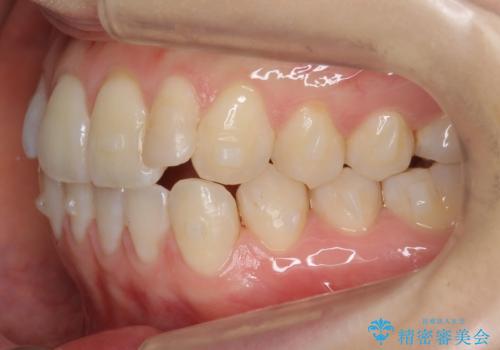

前歯が気になる 大人のマウスピース矯正 矮小歯を整える

- 前歯の並びを主訴に来院。

マウスピースで歯を抜かずに治療しています。

左上の前歯が飛び出しており、唇が笑った時に引っかかっていたのが解消しています。

左上の前歯は小さいため、(矮小歯)左右対称になるようにセラミックで形を修正する治療も併用しています。

歯を大きくかぶせるスペースを作るため、右上の奥歯を後ろに下げています。

左にずれていた上の正中も揃い、大変喜んでいただきました。